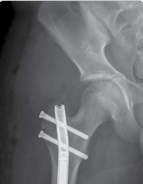

| Surgical techniques have changed in an attempt to minimise these complications. The use of intramedullary implants reduces fixator time and provides regenerate stability. Lengthening over a nail or lengthening followed by nailing still incorporates the use of an external fixator. The development of intramedullary lengthening nails eliminates the need for the external fixator. The initial designs utilised a ratchet mechanism that required rotation of the limb and bone segments to lengthen. A change in design was made where transcutaneous electrical energy drove a motor to improve control in lengthening. The latest and most popular implant is the Precice Intramedullary Lengthening Sysytem (NuVasive Inc., California). This is a magnet-operated telescopic internal lengthening device with an outer casing of titanium alloy (Ti-6Al-4V). A cylindrical rare earth magnet is connected to a gear box and screw shaft assembly within the nail. Two rotating rare earth magnets in an external remote controller (ERC) | |||

| Figure 15.14 Precice lengthening nail. | |||

| Figure 15.15 Growth arrest in a 12-year-old child. are held over the magnet within the nail, resulting in rotation of the implant magnet which can either lengthen or shorten the nail with sub-millimeter accuracy. Early results are favourable confirming faster regenerate healing times, less complications, better cosmetic results and more favourable patient outcomes compared to lengthening using an external fixator (Figures 15.14–15.17). | |||